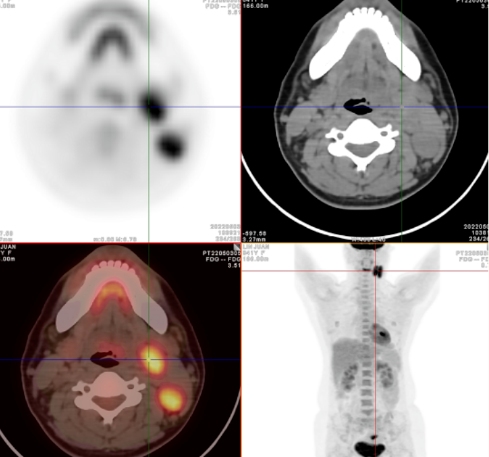

Fig.118F-FDG PET/CT 显像图像

Fig.2右侧咽旁间隙见一FDG摄取异常增高淋巴结 ,SUVmax6.6,短径约9mm

Fig.3右颈胸锁乳突肌深部Ⅱ-Ⅲ区多发增大淋巴结,FDG摄取异常增高,部分融合 SUVmax7.7,最大短径约13mm

Fig.4左颈Ⅱ区FDG摄取稍增高淋巴结SUVmax2.8,短径7mm

Fig.5鼻咽左侧咽隐窝稍变浅,FDG摄取略高SUVmax2.9

Fig.6双侧腭、舌扁桃体增大,FDG摄取增高SUVmax10.1,右侧为著

● 病例1:右侧腭扁桃体术后病理为鳞癌